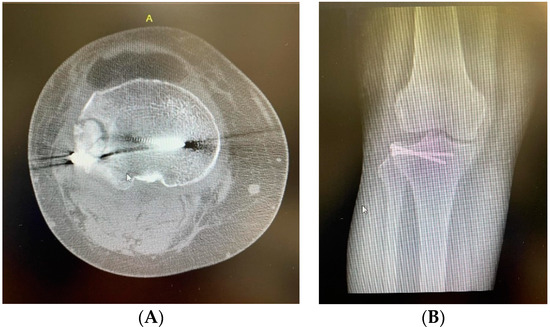

Sticky Bone as a New Type of Autologous Bone Grafting in Schatzker Type II Tibial Plateau Fracture Case Report

2. Clinical Case Presentation